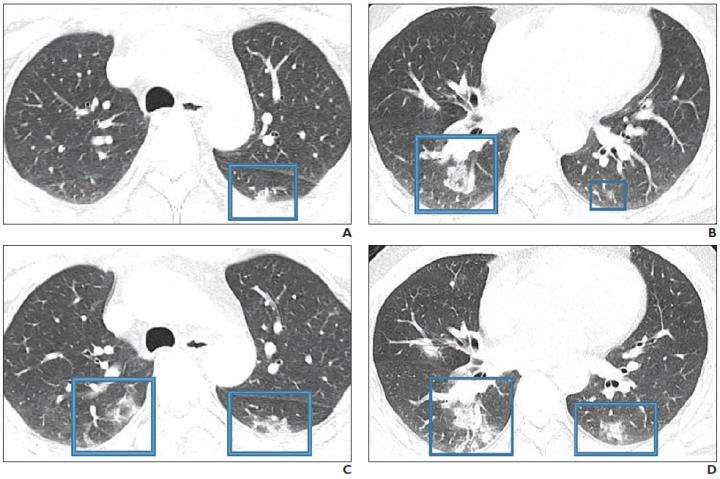

Leesburg, VA, February 28, 2020--Although the imaging features of novel coronavirus disease 2019 (COVID-19) are variable and nonspecific, the findings reported thus far do show "significant overlap" with those of severe acute respiratory syndrome (SARS) and Middle East respiratory syndrome (MERS), according to an ahead-of-print article in the American Journal of Roentgenology (AJR).

COVID-19 is diagnosed on the presence of pneumonia symptoms (e.g., dry cough, fatigue, myalgia, fever, dyspnea), as well as recent travel to China or known exposure, and chest imaging plays a vital role in both assessment of disease extent and follow-up.

As per her review of the present clinical literature concerning COVID-19, Melina Hosseiny of the University of California at Los Angeles concluded: "Early evidence suggests that initial chest imaging will show abnormality in at least 85% of patients, with 75% of patients having bilateral lung involvement initially that most often manifests as subpleural and peripheral areas of ground-glass opacity and consolidation."

Furthermore, "older age and progressive consolidation" may imply an overall poorer prognosis.

Unlike SARS and MERS--where initial chest imaging abnormalities are more frequently unilateral--COVID-19 is more likely to involve both lungs on initial imaging.

"To our knowledge," Hosseiny et al. continued, "pleural effusion, cavitation, pulmonary nodules, and lymphadenopathy have not been reported in patients with COVID-19."

Ultimately, the authors of this AJR article recommended CT for follow-up in patients recovering from COVID-19 to evaluate long-term or even permanent pulmonary damage, including fibrosis--as seen in SARS and MERS infections.